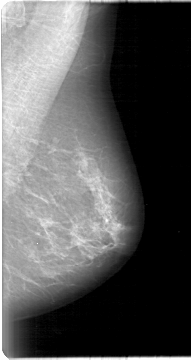

D_4011_1.LEFT_MLO

LEFT_MLO LINES 5386 PIXELS_PER_LINE 2851 BITS_PER_PIXEL 12 RESOLUTION 43.5 NON_OVERLAY